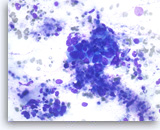

Ductal adenocarcinoma #1,

Pancreas FNA, Direct Smear.

The aspirates show single and clusters of malignant epithelial cells. The clusters are three-dimensional with overlapped nuclei. A few histiocytes are seen in the background.

20X

Ductal adenocarcinoma #1,

Pancreas FNA, Direct Smear.

The aspirates show single and clusters of malignant epithelial cells. The clusters are three-dimensional with overlapped nuclei. A few histiocytes are seen in the background.

20X